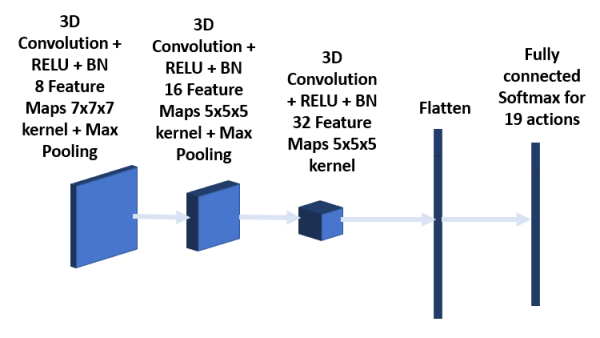

The policy network shown in Figure 5 is made up of three 3D convolution layers together with batch normalization and RELU activation. The kernel sizes of the first, second and third convolution layers are 7x7x7, 5x5x5 and 3x3x3 respectively. The network takes as input the data within the bounding box shrunk by half. The convolution layers are followed first by a fully connected layer and then by a softmax layer for 19 possible actions. The loss function used is mean square error.